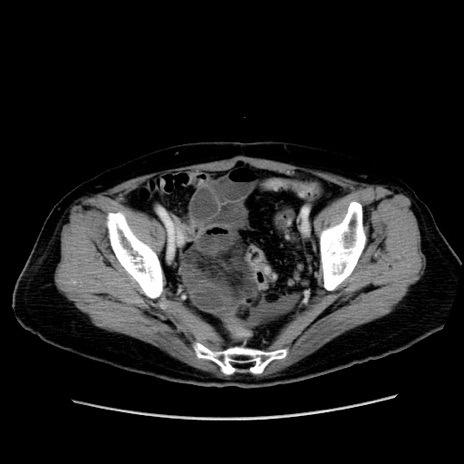

症例19(横断像)

【症例】80歳代女性

【主訴】下腹部痛

【現病歴】約8時間前より下腹部痛の出現あり、救急外来受診。

【既往歴】両側付属器切除

【身体所見】意識清明、下腹部正中に手術痕あり、その部位に一致して圧痛と反跳痛あり。腸蠕動音は亢進。

【データ】WBC 9300、CRP 0.15